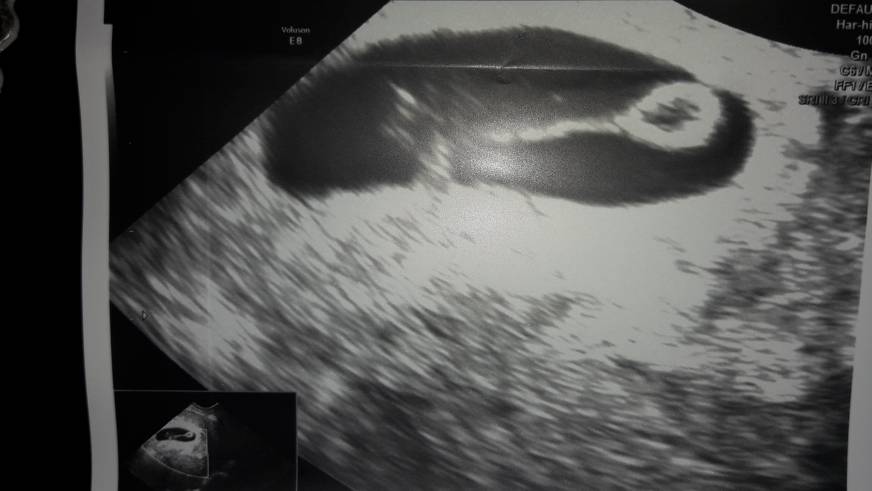

Starania to jedno ale ja już się boję o utrzymanie ciąży....